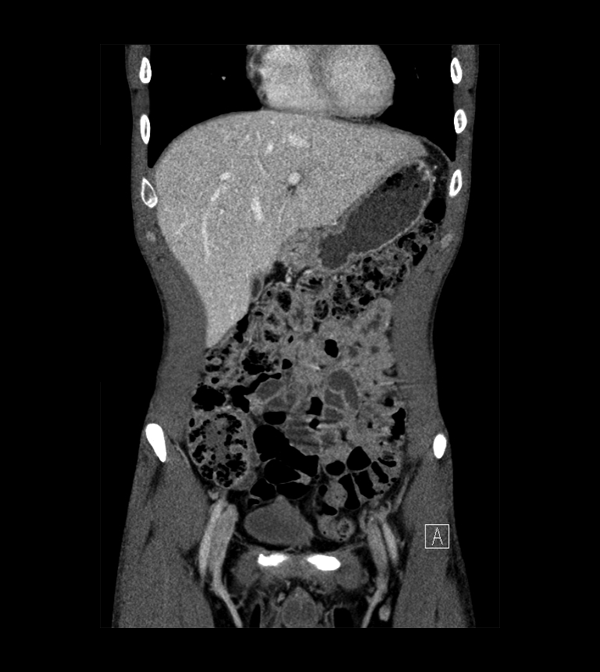

Body

Covers abdominal CT anatomy.